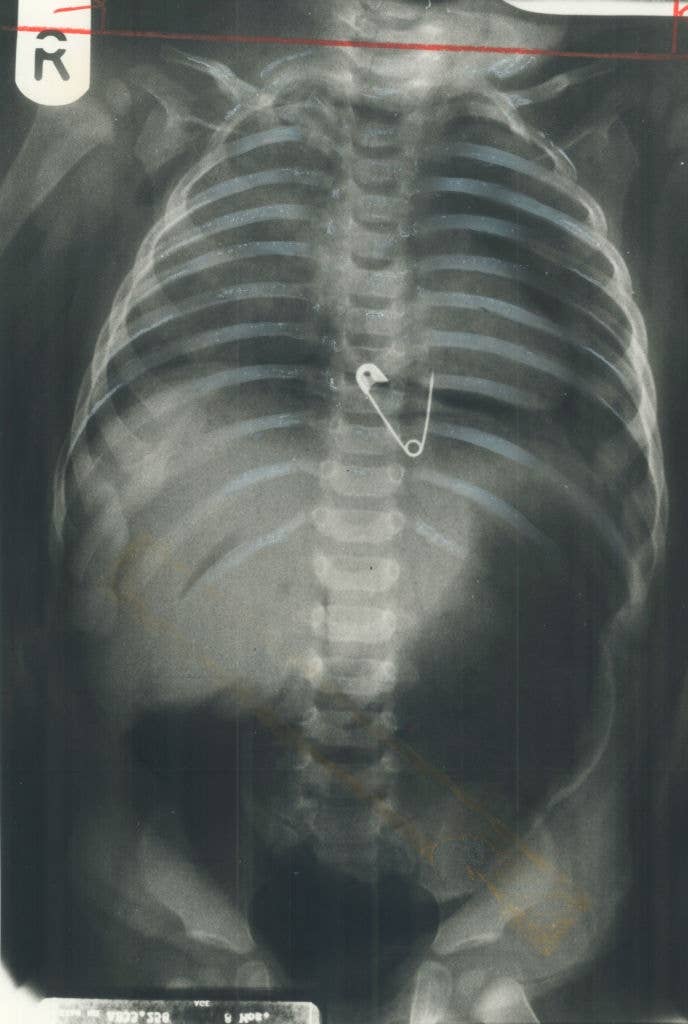

Surgeons, What's The Most Jaw-Dropping Thing You've Seen In The OR?